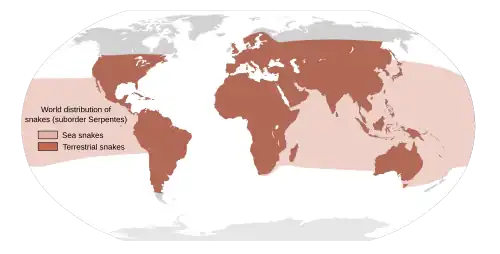

Snakes bite both as a method of hunting and as a means of protection.[14] Risk factors for bites include working outside with one's hands such as in farming, forestry, and construction.[1][3] Snakes commonly involved in envenomations include elapids (such as kraits, cobras and mambas), vipers, and sea snakes.[7] The majority of snake species do not have venom and kill their prey by constriction (squeezing them).[2] Venomous snakes can be found on every continent except Antarctica.[14] Determining the type of snake that caused a bite is often not possible.[7] The World Health Organization says snakebites are a "neglected public health issue in many tropical and subtropical countries",[13] and in 2017, the WHO categorized snakebite envenomation as a Neglected Tropical Disease (Category A). The WHO also estimates that between 4.5 and 5.4 million people are bitten each year, and of those figures, 40–50% develop some kind of clinical illness as a result.[15] Furthermore, the death toll from such an injury could range between 80,000 and 130,000 people per year.[16][15] The purpose was to encourage research, expand the accessibility of antivenoms, and improve snakebite management in "developing countries".[17]

The number of venomous snakebites that occur each year may be as high as five million.[3] They result in about 2.5 million envenomations and 20,000 to 125,000 deaths.[3][14] The frequency and severity of bites vary greatly among different parts of the world.[14] They occur most commonly in Africa, Asia, and Latin America,[3] with rural areas more greatly affected.[3][13] Deaths are relatively rare in Australia, Europe and North America.[14][18][19] For example, in the United States, about seven to eight thousand people per year are bitten by venomous snakes (about one in 40 thousand people) and about five people die (about one death per 65 million people).[1]

.svg.png)

Earlier estimates for snakebite vary from 1.2 to 5.5 million, with 421,000 to 2.5 million being envenomings, and causing 20,000 to 125,000 deaths.[3][14] More recent modelling estimates that in 2019, about 63,400 people died globally from snakebite, with 51,100 of these deaths happening in India.[81] Since reporting is not mandatory in much of the world, the data on the frequency of snakebites is not precise.[14] Many people who survive bites have permanent tissue damage caused by venom, leading to disability.[18] Most snake envenomings and fatalities occur in South Asia, Southeast Asia, and sub-Saharan Africa, with India reporting the most snakebite deaths of any country.[14] Available evidence on the effect of climate change on the epidemiology of snakebite is limited but it is expected that there will be a geographic shift in the risk of snakebite: northwards in North America and southwards in South America and Mozambique, and increase in the incidence of bite in Sri Lanka.[82]

Most snakebites are caused by non-venomous snakes. Of the roughly 3,000 known species of snake found worldwide, only 15% are considered dangerous to humans.[2][14] Snakes are found on every continent except Antarctica.[14] The most diverse and widely distributed snake family, the colubrids, has approximately 700 venomous species,[83] but only five genera—boomslangs, twig snakes, keelback snakes, green snakes, and slender snakes—have caused human fatalities.[83]

Worldwide, snakebites occur most frequently in the summer season when snakes are active and humans are outdoors.[14][84] Agricultural and tropical regions report more snakebites than anywhere else.[14][28] In the United States, those bitten are typically male and between 17 and 27 years of age.[2][84][85] Children and the elderly are the most likely to die.[2][49]